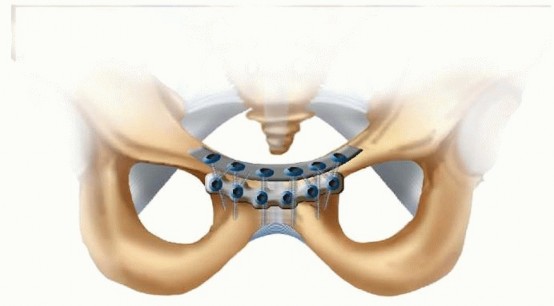

Double-Plating Technique

Tile 13 described placing a second plate anteriorly if there is no posterior fixation to be placed in vertically unstable patterns

( TECH FIG 6).

This technique can also be used if insufficient purchase is achieved with initial plate placement.

TECH FIG 6 • Example of double plating described by Tile.13

In placing the anterior plate, care must be taken in placing screws around the screws of the other plate. The same sequence of screw placement should be followed, with the medial screws placed first and subsequent screws placed laterally. 1. ## Wound Closure Once the symphysis is reduced and the plate is in place, a Hemovac is placed in the space of Retzius, between the bladder and the symphysis, and is brought through the rectus fascia. After drain placement, the wound is pulse lavaged and the rectus fascia is closed with running heavy absorbable sutures. Care should be taken not to include too many muscle fibers to avoid muscle necrosis. Interrupted sutures are used at the distal end to provide a sideto-side closure of the avulsed side. The skin is then closed with subcutaneous sutures and staples. ## PEARLS AND PITFALLS Setup ▪ It is important to make sure that adequate fluoroscopic AP, inlet, and outlet views can be obtained in the operating room before draping. Reduction ▪ Reduction is confirmed under direct vision as well as on inlet and outlet views of the pelvis. The C-clamp can also be used to maintain reduction before plating if conventional clamps cannot hold the reduction.